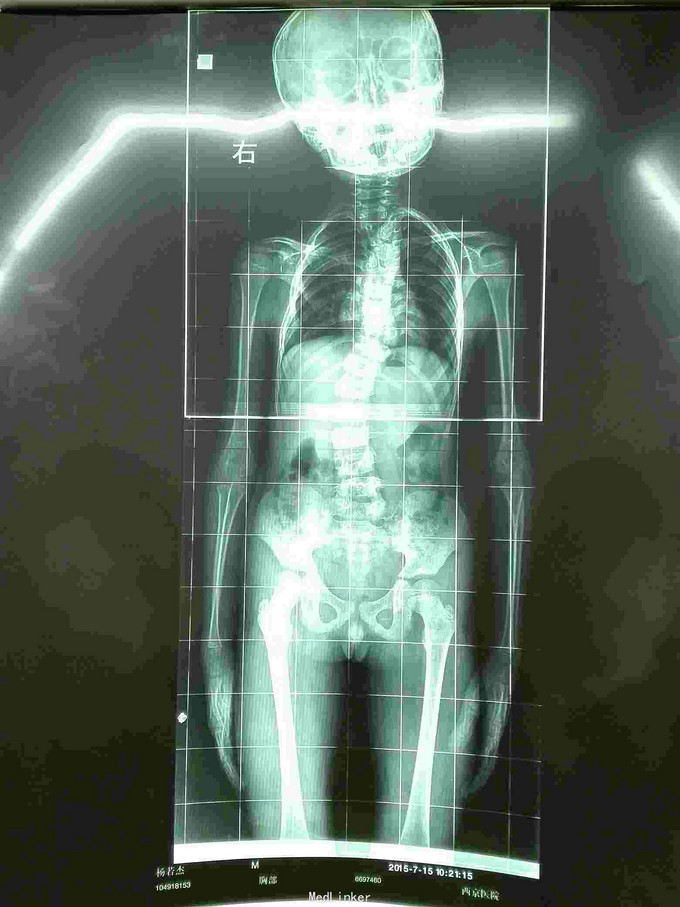

先天脊柱畸形

先天脊柱畸形8年。

严重脊柱畸形病例

先天性脊柱侧凸畸形

脊柱先天畸形